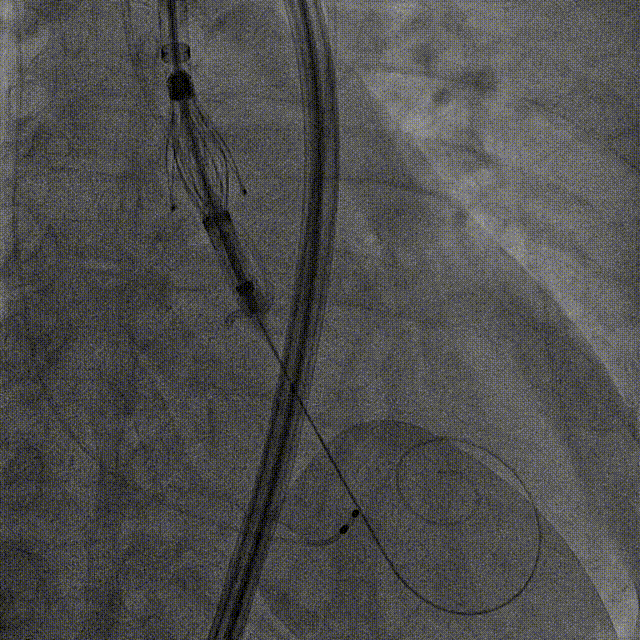

瓣膜调弯后解离

瓣膜右窦中心调整

定位键窦不对齐

灵活旋转操作

确认窦对齐

入窦

无窦超选验证

左窦超选验证

一键释放

术后造影